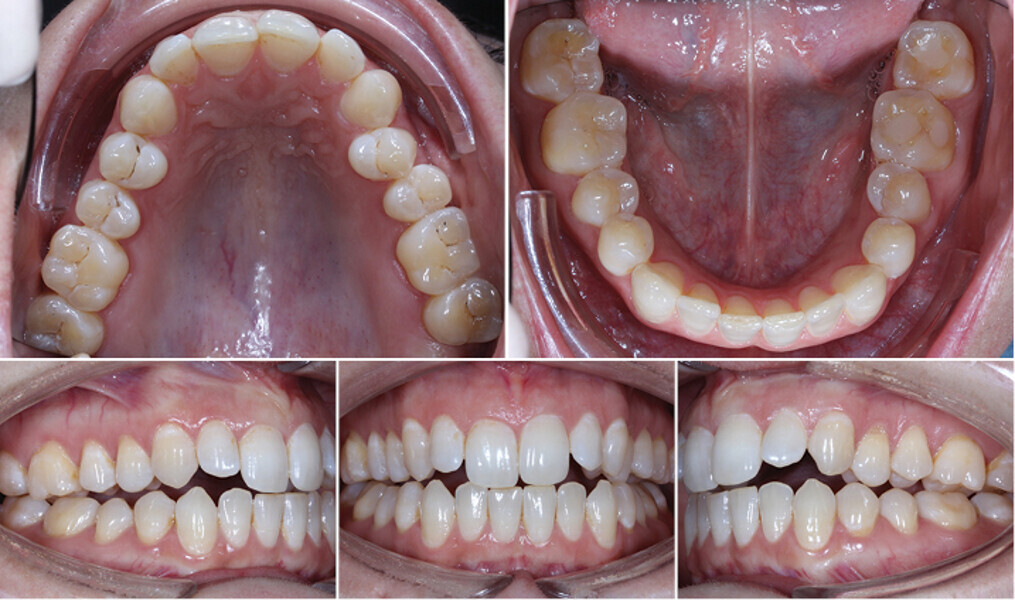

Řešení otevřeného skusu u dospělého pomocí Insignia™ systému a Straight-Wire™ finishingu